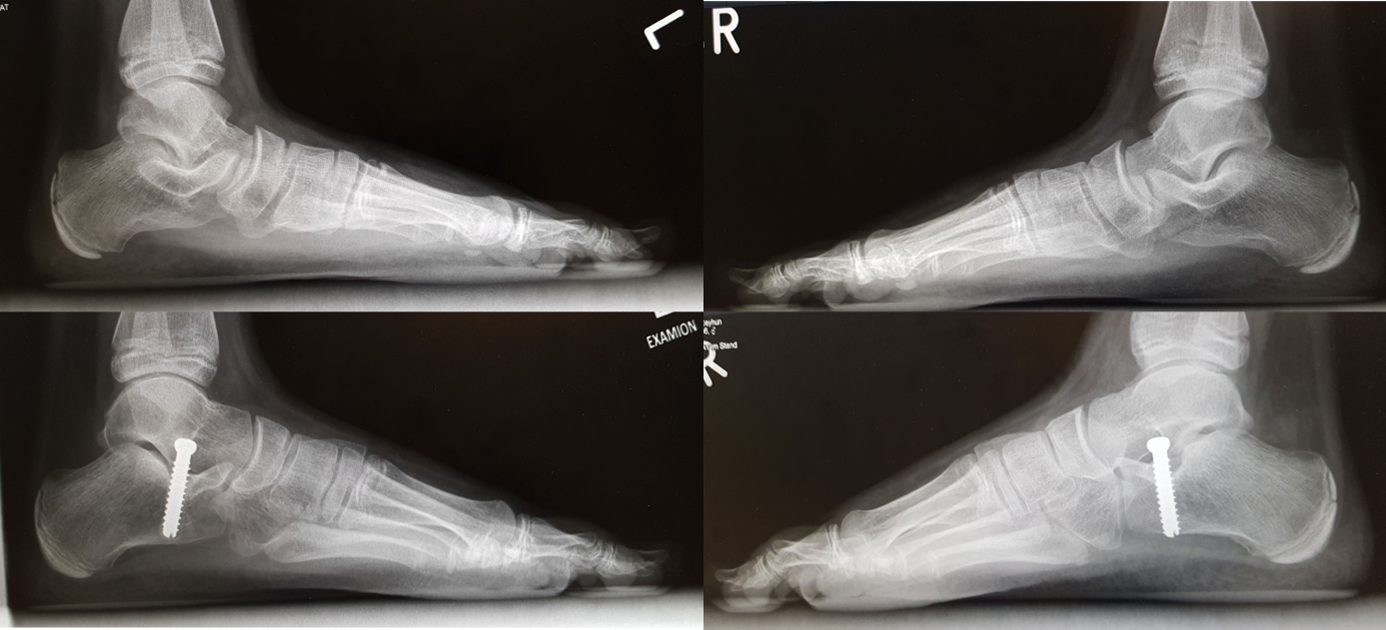

Der schwere kindliche Plattfuß mit dem so genannten vertikalen Sprungbein muss operiert werden. Bei der Plattfußoperation werden Knochen durchtrennt, versetzt und zusammengeschraubt

Der kindliche Plattfuß kein Grund zur Dr. Göddertz. Informieren Sie sich vor einer Plattfuß Operation immer über mögliche OP-Methoden und ob bei Ihrer Operation durch Knochenschrauben (Schrauben aus menschlichem Knochen), wie der Shark Screw®, eine mögliche weitere Operation zur Metallentfernung, wie bei Schrauben und Platten aus Metall vermieden werden kann. Sehnen, Gelenkkapseln und Bänder werden abgetrennt und wieder angenäht bzw